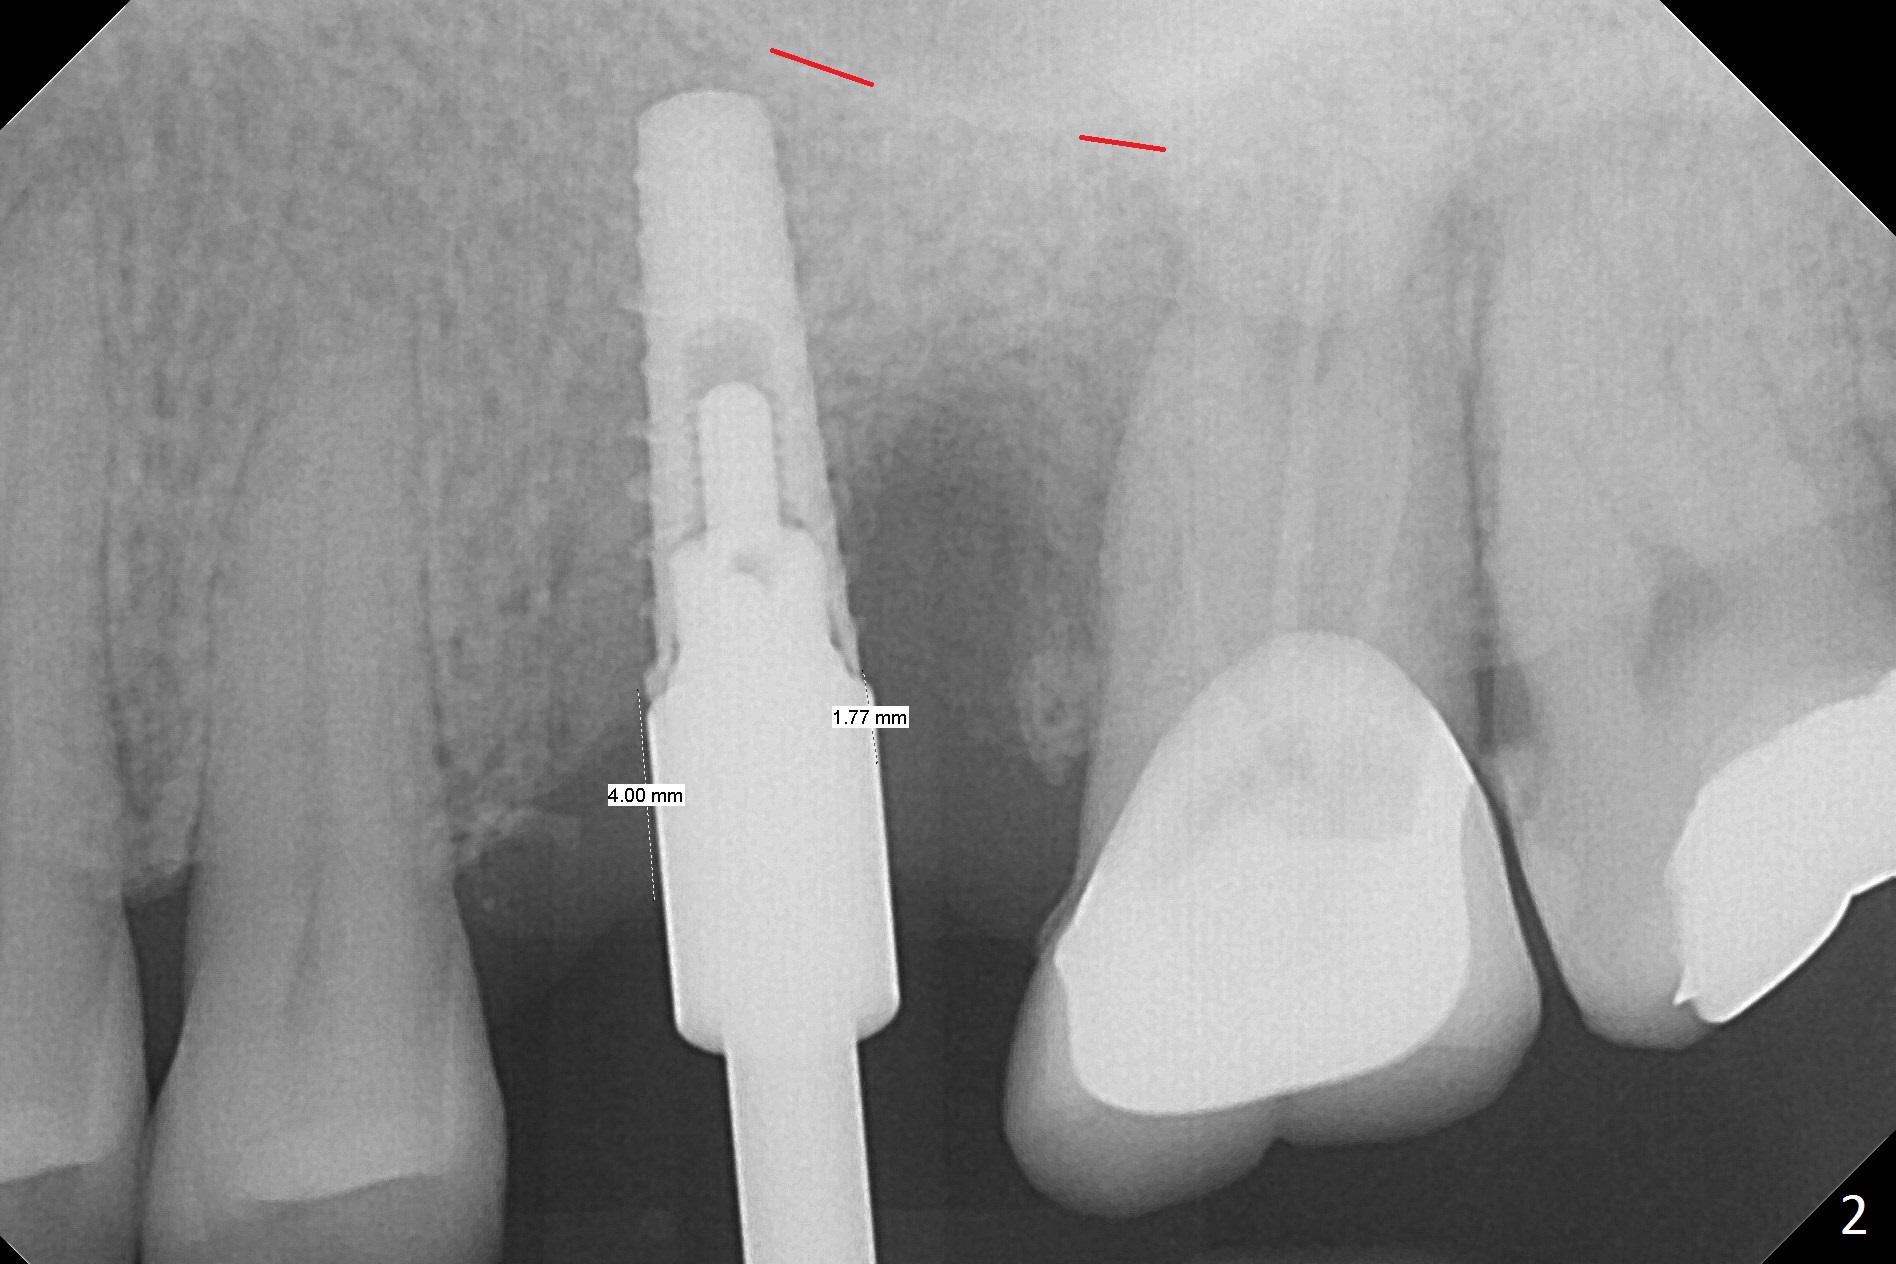

Magic Split is used to start access (flapless) and initial bone expansion at #14. The split does not go deep, since bone density is high in the deep portion. A 1.6 mm drill has to be used for 13 mm (Fig.1). Note the low bone density in the distobuccal socket (*). Later the osteotomy extends to 15 mm (gingival level). After 3.8 mm Magic Drill (MD) for 15 mm, a 4x11 mm dummy implant is placed with insertion torque of 60 Ncm (implant motor, Fig.2). After 4.3 mm MD, a 4.5x11 mm IBS implant is placed with insertion torque of 60 Ncm for implant motor >40 Ncm for torque wrench (Fig.3). The implant seems to be placed deep, but the buccal plate feels to be low. Following bone graft buccally, especially distobuccal (Fig.4,5 ^), a 5x4(3) mm abutment is placed. The buccal gingiva is torn during bone graft (Fig.6 >). Periodontal dressing is applied around the abutment (for increased retention) for wound protection.